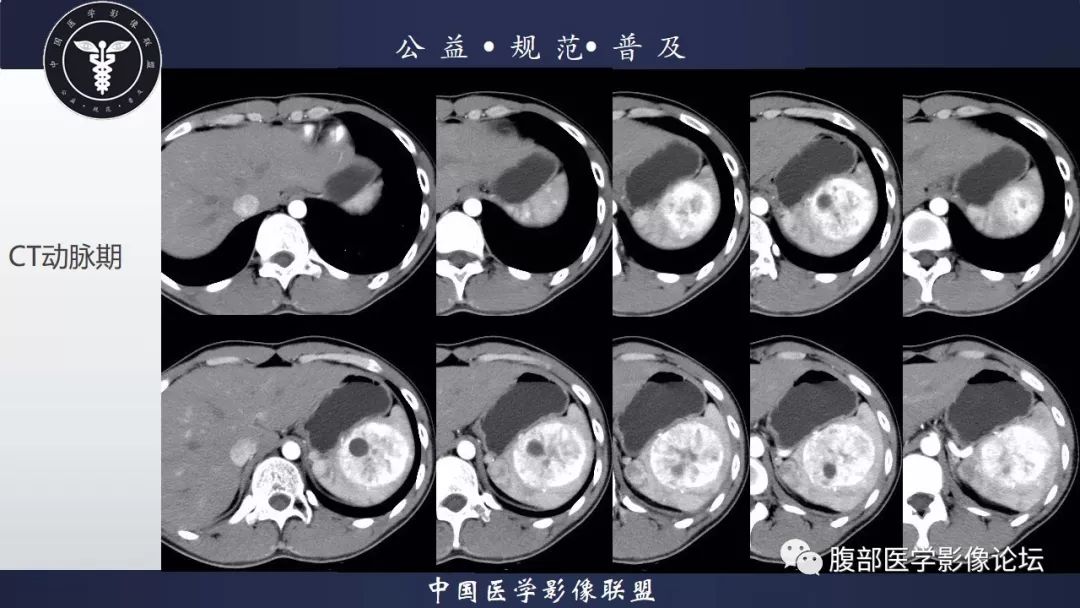

脾脏窦岸细胞血管瘤三例讨论及文献复习